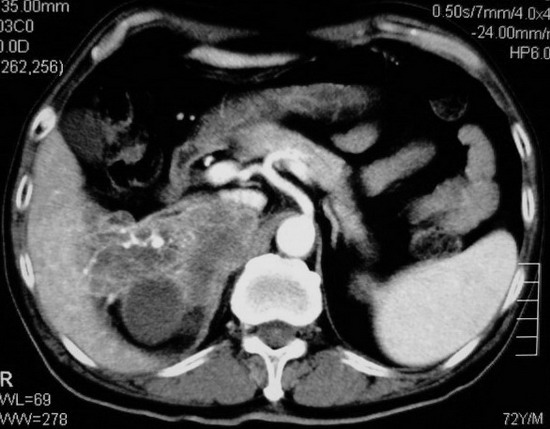

以下是引用杀毒软件在2008-11-17 19:15:00的发言:[br]考虑------右肾癌合并肾静脉---同侧肾上腺受侵可能性大

以下是引用zjzjr在2008-11-17 20:45:00的发言:[br]考虑------右肾癌合并肾静脉---同侧肾上腺受侵可能性大及腹膜后淋巴结转移.